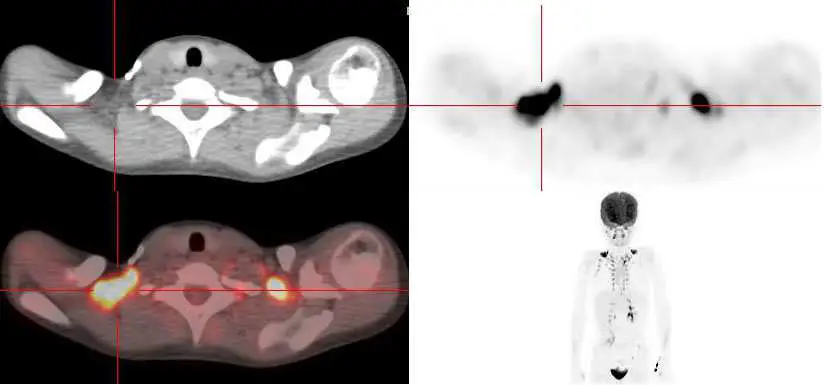

本圖為 18F-FDG PET/CT 影像,包含四個視窗:

- 左上:CT 橫斷面(頸胸交界區),可見雙側鎖骨上脂肪組織。

- 左下:PET/CT 融合橫斷面,可見雙側鎖骨上及脊椎旁有強烈且對稱的熱區(橘紅色),對應位置為脂肪組織而非肌肉或淋巴結。

- 右上:PET 橫斷面,清楚顯示雙側對稱攝取。

- 右下:全身 MIP(maximum intensity projection)影像,可見頸部、鎖骨上及脊椎旁呈雙側對稱線狀/帶狀分布的 FDG 高攝取,沿頸椎及上胸椎兩旁延伸,此分布型態高度符合 BAT 活化,而非惡性腫瘤(惡性病灶通常不對稱、呈局灶性)。

影像重點:對稱性、位於脂肪分布區(而非淋巴結位置)、沿頸部及脊椎旁分布 → BAT 活化的特徵性表現。